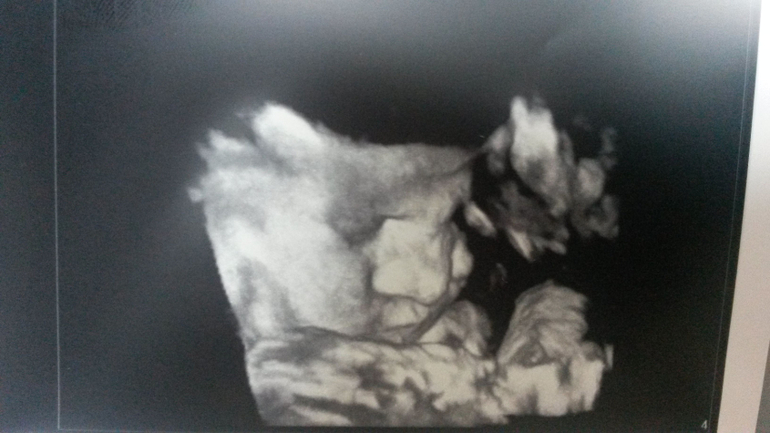

39-я неделя и мы на финишной прямой + фото

Насть, ну мне кажется вы прям хорошо набрали, наверное к родам около 3 кг будете) И на узи щечки у вас хорошенькие) Вам когда пдр ставят?Меня тоже смотрели на кресле, но пока тишина. Я в общем то не расстроилась по этому поводу, только из-за шейки немного переживаю. Ребенок практически на выходе, а шейка не готова абсолютно(